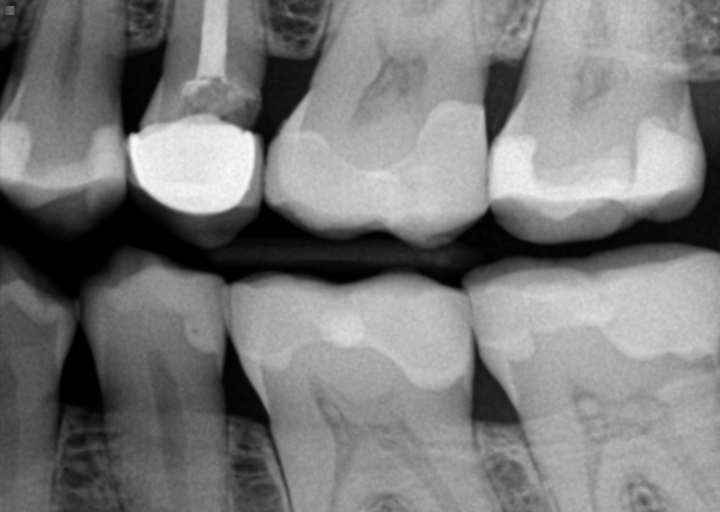

CROWN STRUCTURE BROKEN

My first molar crown came off due to a broken tooth root structure, thus leaving a deep cavity, with very short and small root pieces protruding out of the cavity. Each time I eat, food accumulates in the cavity; thus, I clean well the cavity after each meal, which is causing gum inflammation in the perimeter. Also, I have not had the adjacent piece (premolar) for a long time, which has never bothered me. Pease give me your best advice, considering I would like to cover the cavity permanently in order to avoid food accumulation. Note, I wish to avoid any invasive procedures, such as implant, or the constant discomfort of having a bridge. Thank you

The first step is to have a dental radiograph taken in order to determine if the tooth or teeth are restorable. If they are broken at the gum line as a result of extensive decay, the decay may be on the root surfaces, below the level of the bone. With this type of decay, the long term prognosis is poor and extensive dental treatment would be needed in order to save the teeth. If there isn't root caries present, the teeth may be restorable with full coverage crowns. The longer you wait, the more tooth structure you will loose. This will lead to more necessary dental treatment or unwanted periodontal issues. It is better to go sooner in order to have multiple options for restoring your teeth.